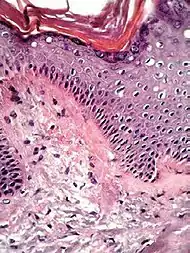

Spongiotic dermatitis

It is characterized by epithelial intercellular edema.[2]

| Generally/Not otherwise specified[notes 2] | Typical findings:[2]

|

Typical findings:[2]

|

Typical findings:[2]

PAS stain is essential to exclude fungal infection.[2] |

Subacute Subacute |

|

| Allergic/contact dermatitis or atopic dermatitis | As above. Eosinophils may be present in the dermis and epidermis (eosinophilic spongiosis).[2] |  Allergic dermatitis Allergic dermatitis |

.jpg.webp) Atopic dermatitis Atopic dermatitis | ||

In addition to above, an unspecific spongiotic dermatitis can be consistent with nummular dermatitis, dyshidrotic dermatitis, Id reaction, dermatophytosis, miliaria, Gianotti-Crosti syndrome and pityriasis rosea.[2][notes 2]